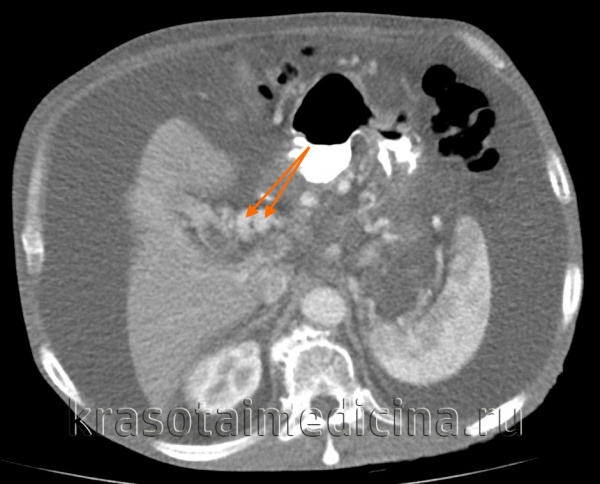

КТ ОБП. Этот же пациент, расширенный левый долевой ствол воротной вены (синяя стрелка) с периваскулярным отеком (желтая стрелка).